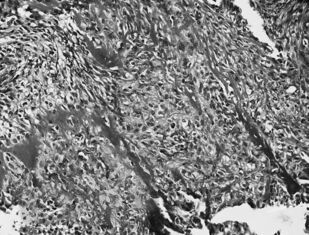

В книге представлены возможности морфологических исследований (патолого-анатомических и цитологических) в определении морфофункционального состояния клеток и тканей двух типов первичных злокачественных новообразований костей до проведения, в динамике и после завершения курса лучевой терапии. Показана значимость использования полученных данных в выборе метода лечения, в т. ч. и лучевого, в оценке прогноза и эффективности лучевой терапии при злокачественных новообразованиях костей.